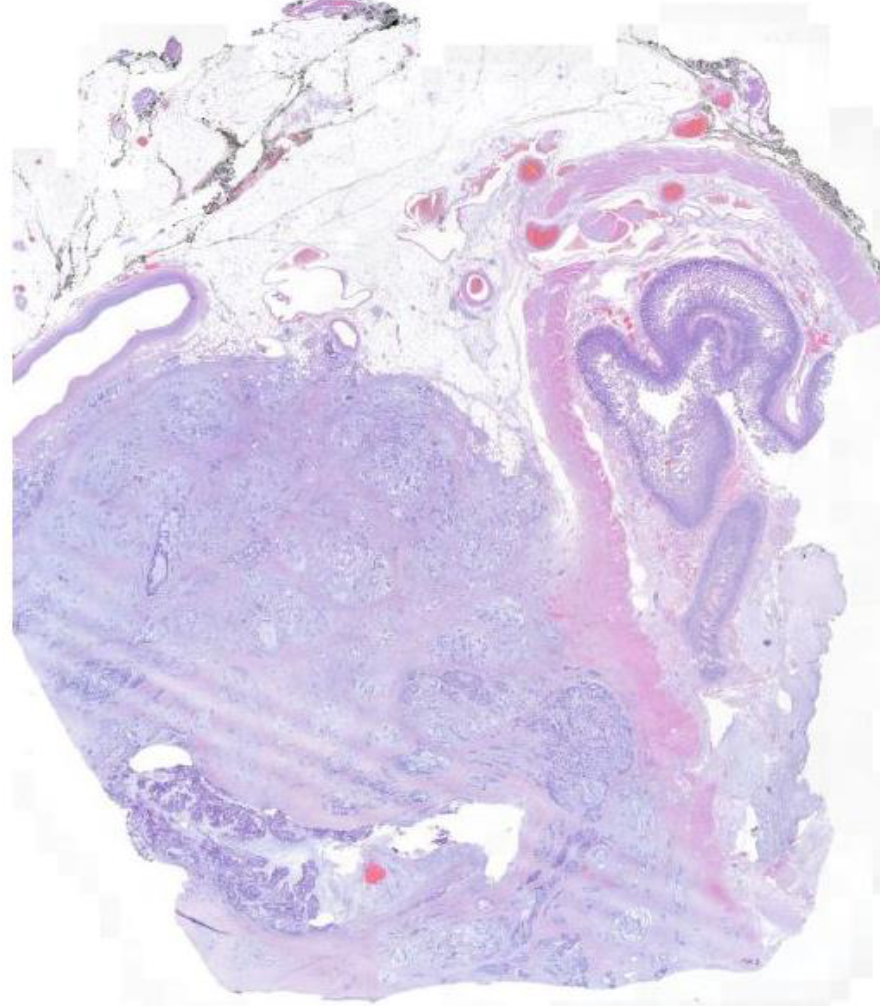

Diagnose?

Plattenepithelkarzinom der Zervix